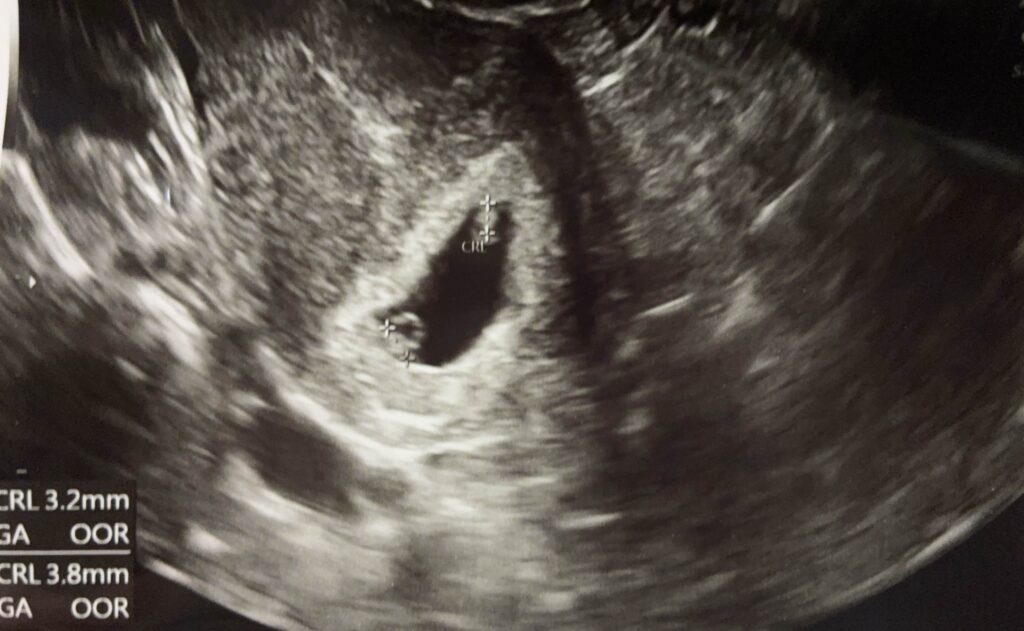

よく画面を見ると一つの袋の中に二つ小さい丸があり、トクトクと動いていました。

こちらがエコー写真です